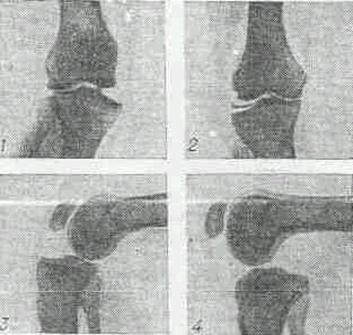

Рис 5 Рентгенограмма коленного сустава при различных повреждениях коленного сустава

1 - разрыв большеберцовой коллатеральной связки - отклонение голени к наружи;

2 - разрыв малоберцовой коллатеральной связки - отклонение голени кнутри при нагрузке;

3 - повреждение передней крестообразной связки, патологическое увеличение выдвижение голени кпереди ("симптом переднего выдвинутого ящика");

4 - повреждение (разрыв) задней крестообразной связки, патологическое увеличение выдвижение голени кзади ("симптом заднего выдвинутого ящика").